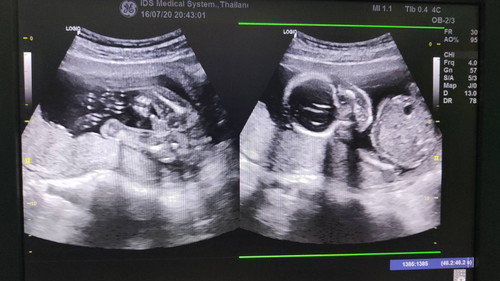

แบบนี้ผู้ชายหรือผู้หญิงคะ

ไปซาวด์มาหมอ2คนบอกเป็นผู้ชายทั้ง2คนเลยค่ะ อายุครรภ์ประมาณ 18-19 วีคค่ะ 😊 ขอประสบการณ์แม่ๆทุกคนค่า ❤❤